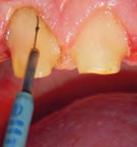

de radiofrecuencia aplicado a la rehabilitación con prótesis fija en un paciente. Caso: rehabilitación con prótesis fija a un paciente masculino de 49 años de edad, militar activo, originario de Tampico, Tamaulipas, que reside en la Ciudad de México. Se presenta a la Unidad de Especialidades Odontólgicas (UEO) referido por su escalón dental para recibir atención en la Especialidad de Prótesis Bucal por pérdida de estructura dental en caras palatinas y oclusales de todos los órganos dentales. Para el desplazamiento gingival en la toma de impresiones se utilizó el equipo de radiofrecuencia (aparato de radiofrecuencia Ellman SURGITRON FFPF EMC, EE. UU.)

Para una rehabilitación con prótesis fija es de suma importancia la toma de impresiones; en este proceso es imprescindible que se realice un desplazamiento gingival, para así dejar visible la línea de terminación de la preparación del pilar; comúnmente se realiza colocando hilo retractor. Es sabido que este procedimiento es tedioso y tardado, requiere destreza y provoca cansancio y estrés tanto para el paciente como para el operador, además del dolor postoperatorio. En el presente caso se llevó a cabo la toma de impresiones para prótesis fija con el apoyo del aparato de radiofrecuencia Ellman modelo Surgitron FFPF EMC (Figura 1), el cual es útil en diversos tratamientos odontológicos. Esta técnica tiene como ventajas el buen control de hemorragia, hemostasia total, fácil manipulación, incisión precisa con mínima destrucción de tejido en el caso de la cirugía puesto que los electrodos son flexibles y pueden moldearse para trabajar con mayor comodidad, campo y área de trabajo

Figura 1. Aparato de radiofrecuencia Ellman Surgitron FFPF EMC, EE. UU. Figura 2. Diferentes puntas para radiofreciencia. Puntas de tungsteno. Figura 3. Punta de trabajo en contacto con el tejido.

Procedimiento de la toma de impresiones

Previo bloqueo regional con lidocaína y epinefrina Zeyco (recomendado para aumentar el grado de electrolito en el tejido), se retiraron restauraciones provisionales, se seleccionó la punta de trabajo (electrodo) para la radiofrecuencia y se colocó en el aparato; una vez conectada la placa (antena), punta de trabajo y pedal, se conectó el aparato a la fuente de energía, se colocó la placa en contacto con la piel del paciente y se encendió el aparato de radiofrecuencia.

Figura 4. Aspecto de los pilares después de la aplicación de la radiofrecuencia. Arco dentario superior e inferior.

Para realizar el desplazamiento gingival se seleccionó en onda parcialmente rectificada (coagulación), potencia baja (2), y se conectó la punta de trabajo en fulguración. El pedal se activó solo cuando la punta de trabajo estuvo muy cerca del contacto con el tejido.

Se pasó la punta seleccionada, únicamente en contacto con el tejido blando cerca del surco gingival en cada pilar preparado (Figura 3). Cuando la punta se encontró en contacto con el tejido, se mantuvo en movimiento constante para evitar el calor excesivo; el movimiento fue en una sola dirección. En el caso del desplazamiento gingival, el diente se tomó como guía para el electrodo.